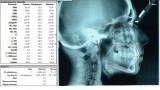

Wykonano także modele diagnostyczne zaartykulowane w relacji centralnej (RC), którą zarejestrowano ze względu na zwiększone napięcie mięśniowe z wykorzystaniem deprogramatora Koisa (ryc. 13-15), oraz zdjęcie pantomograficzne (ryc. 16) i cefalometryczne. Analiza modeli w RC wykazała przesunięcie żuchwy w kierunku doprzednim w stosunku do pozycji maksymalnego zaguzkowania i przedwczesne kontakty funkcjonalne na zębach bocznych, co tłumaczyło obecność odprysków szkliwa na brzegach siecznych górnych zębów (szczególnie wyraźne na zębie 12) (ryc. 14, 17). Na modelach wykonano studium funkcjonalne mające na celu określenie, w jaki sposób można odtworzyć prawidłową funkcję, tzn. uzyskać prawidłowy nagryz pionowy i poziomy oraz prowadzenie przednie (ryc. 18-20).

Minimalne zachodzenie pionowe, a w pozycji RC ustawienie zębów przednich w zgryzie tête à tête nasuwały podejrzenie wady gnatycznej. Analiza zdjęcia cefalometrycznego wykazała wprawdzie prognatyczny typ twarzy, jednak I klasę szkieletową, rotację i translację żuchwy w normie oraz neutralną relację sagitalną i wertykalną podstaw (ryc. 21). Pozwoliło to zaplanować poprawę relacji pomiędzy górnym i dolnym łukiem zębowym przez leczenie ortodontyczne poprzedzone ekstrakcją jednego dolnego zęba siecznego oraz dolnych zębów ósmych. Po leczeniu ortodontycznym zaplanowano chirurgiczne wydłużenie koron przednich zębów górnych i wykonanie adhezyjnych rekonstrukcji ceramicznych na wszystkich zębach szczęki i żuchwy z wyłączeniem drugich zębów trzonowych.